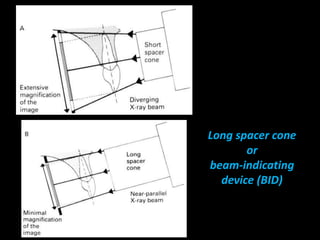

2. The paralleling cone technique provides accurate images with little magnification and no superimposition but is more difficult for patients. The bisecting angle technique is easier for patients but results in more image distortion.